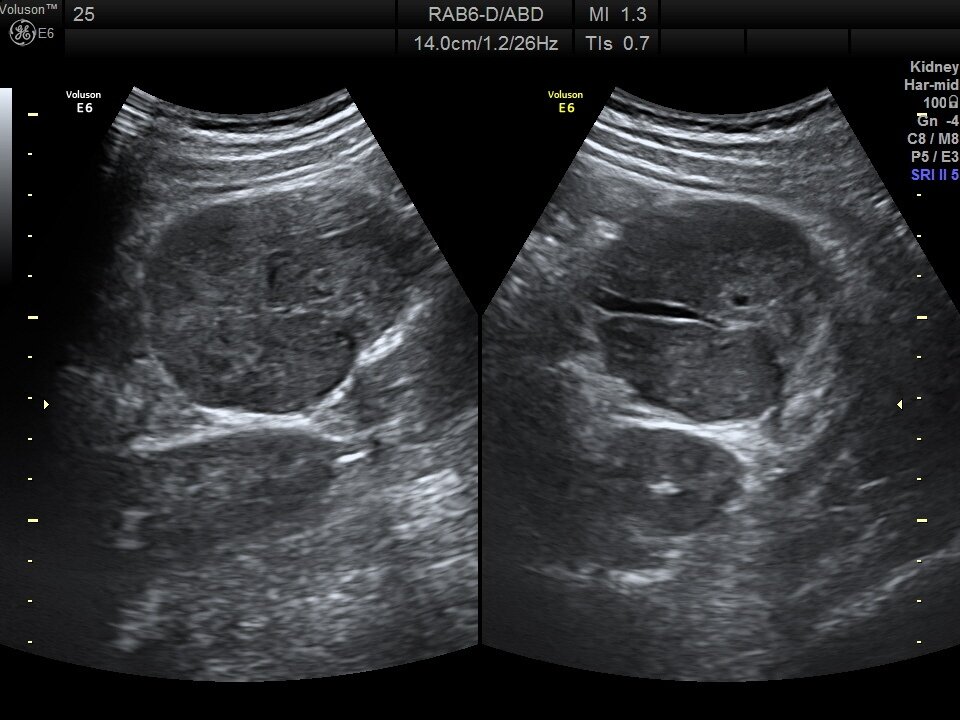

👓Ок, будем посмотреть. Левая почка без особенностей, расположена внизу экрана. Селезёнка не изменена.

🌑А вот в верхней части видно образование округлой формы, сосудами по центру и воротами. При надавливании датчиком болезненно. Размером чуть больше 6см в диаметре. При смене положения подвижно, двигается с брыжейкой кишечника. Мезентериальная лимфоаденопатия.

🧫Чем оно вызвано? Варианты - инфекция и онкопроцесс, болезни крови хотя селезёнка спокойная, первым делом дообследование кишечника.